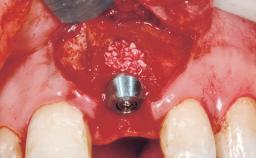

Placement Protocol Immediate implant placement

Tooth Site Maxillary incisor or canine

Socket Morphology Single-root socket

Socket Integrity Sufficient, with intact bone walls

Bone Volume Sufficient, with intact walls